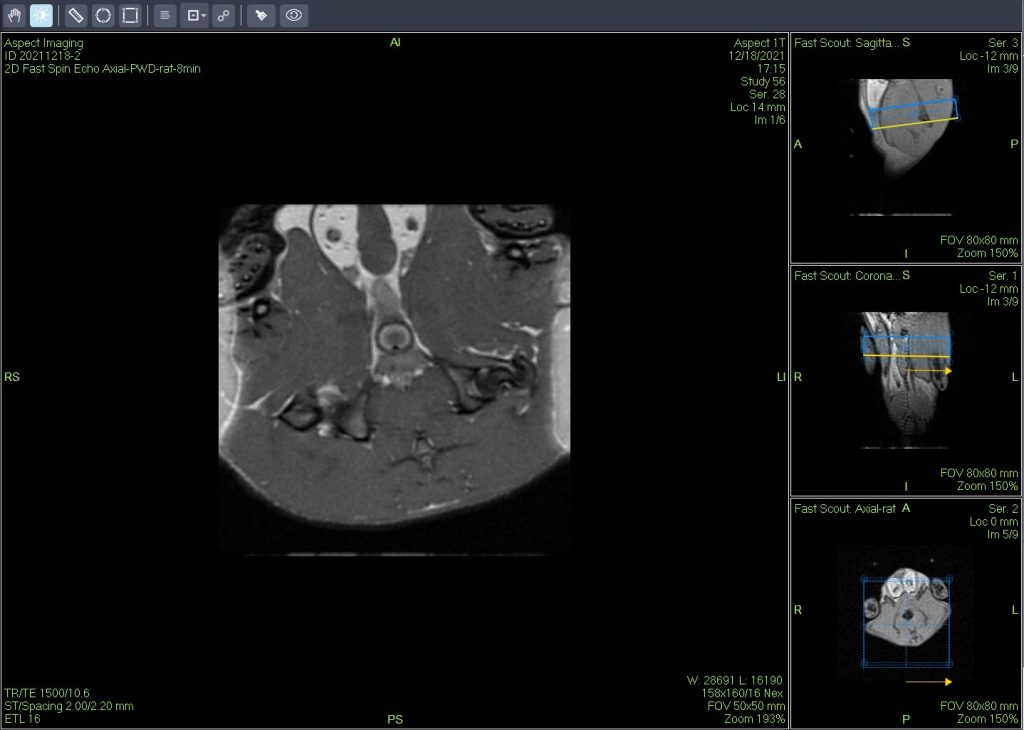

一个新的紧凑型高性能小动物磁共振成像平台(M3),该系统使用一种新的磁铁设计和一套相关的软件,降低了小动物磁共振成像仪的成本和复杂性。

小鼠皮下肿瘤MRI造影成像效果与造影剂代谢过程研究。

使用仪器: 小动物核磁共振成像仪NM20-060H-I 其他相关应用: 核磁共振造影剂弛豫率分析造影剂分析案例 核磁共振成像与分析技术在生命科学领域应用解决方案

使用仪器: 小动物核磁共振成像仪NM21-040H-I 小动物核磁共振成像仪NM20-060H-I 小动物核磁共振成像仪NM42-040H-I